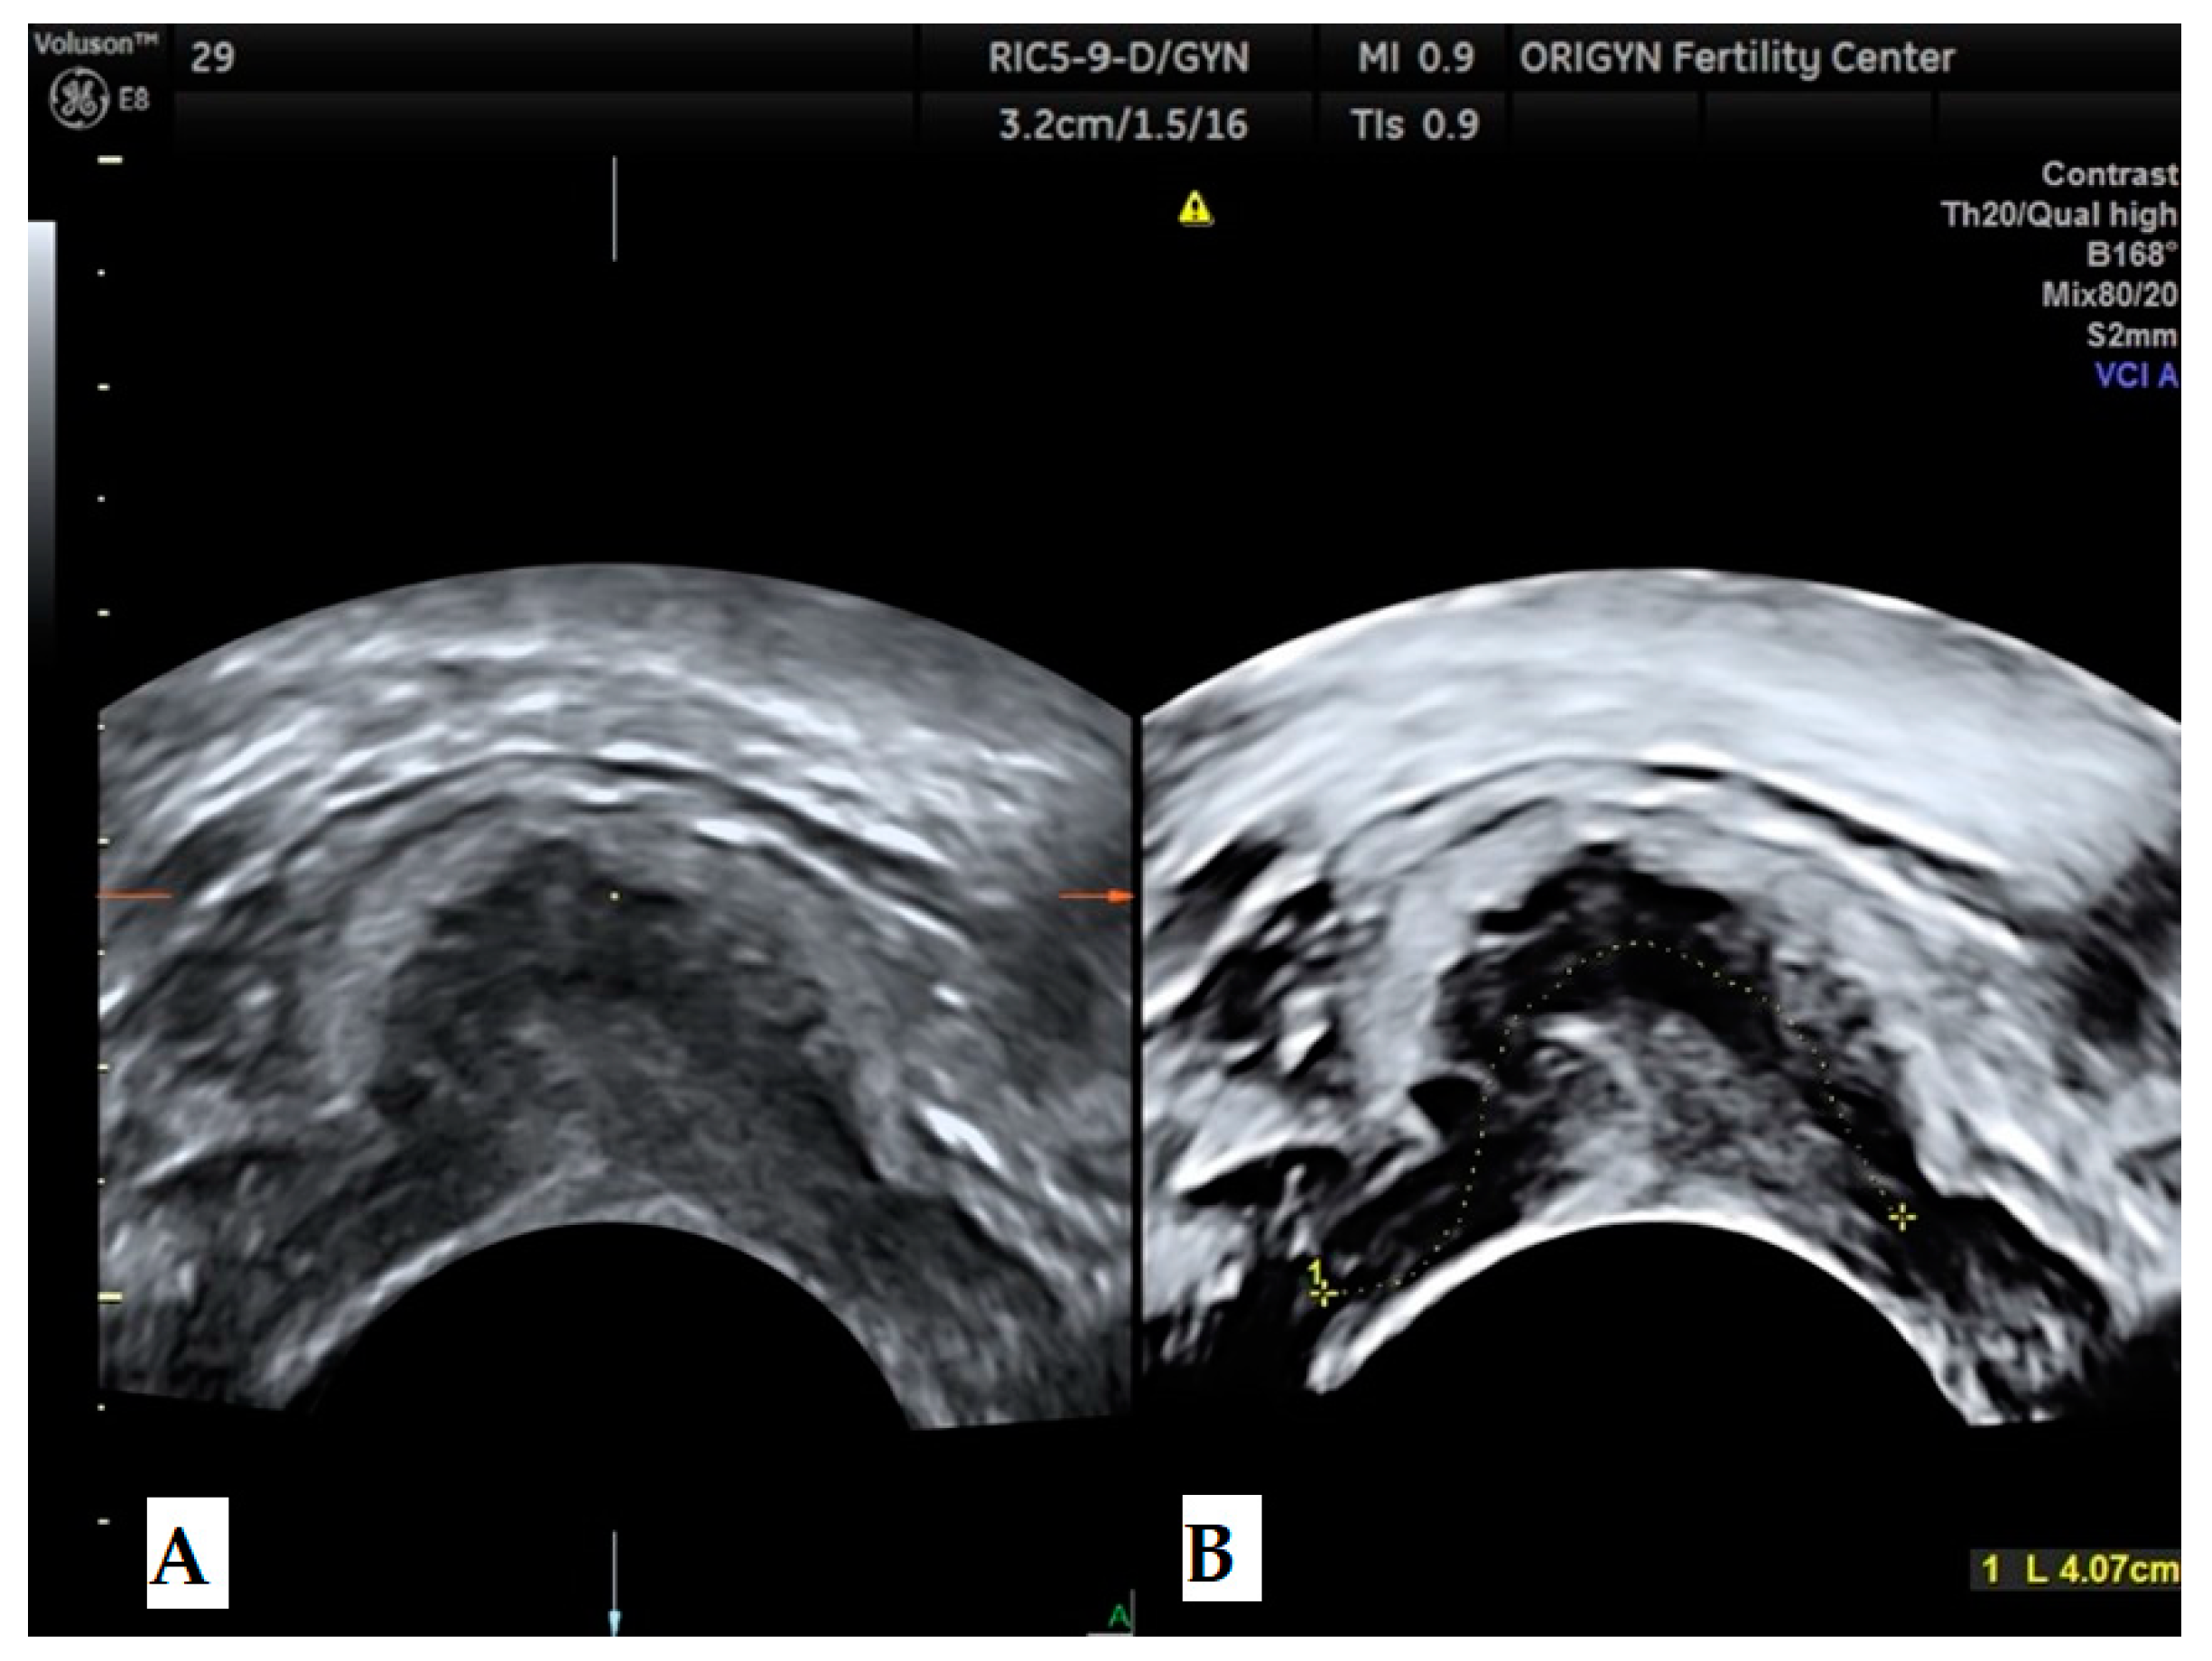

3.1. ADNEXA